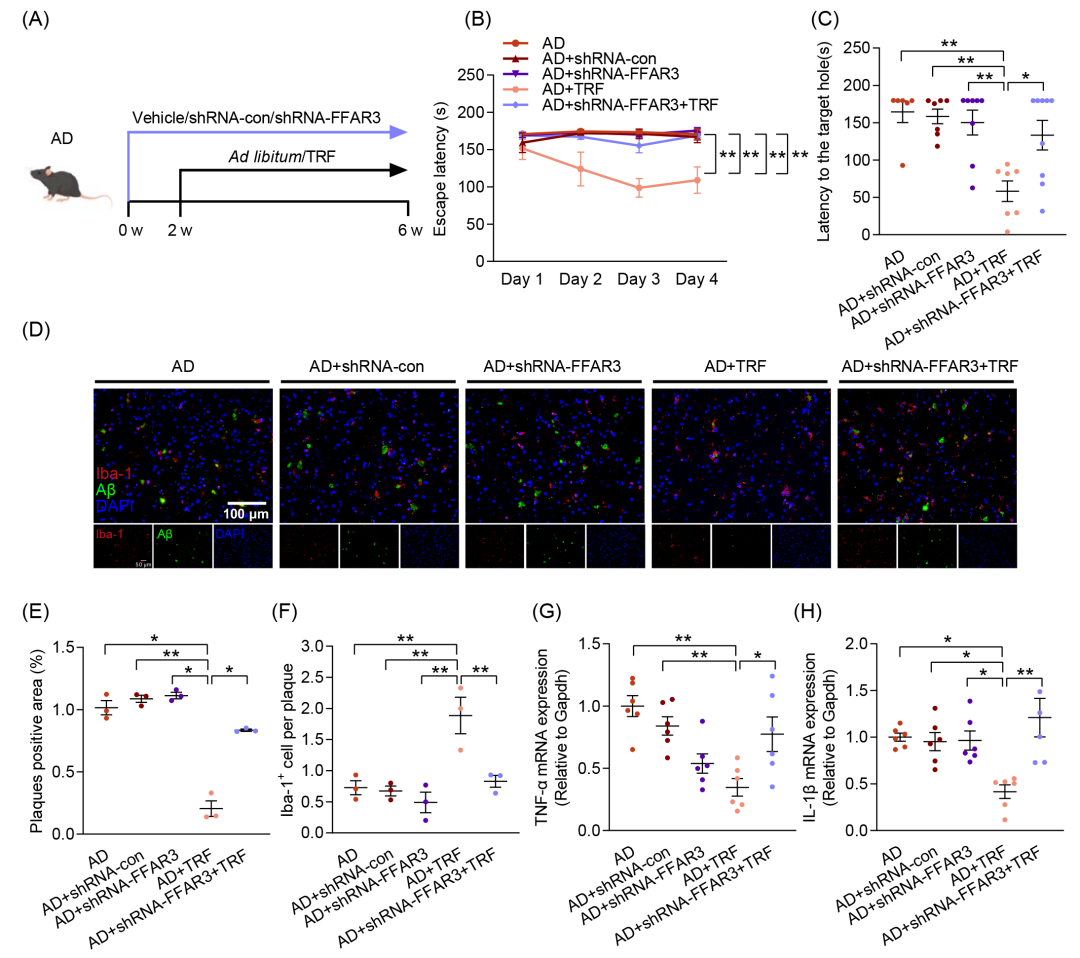

已有研究表明,FFAR3可与PA结合并调节心肌损伤。为探讨FFAR3在TRF干预AD过程中的作用,本研究采用小发夹RNA(shRNA)特异性敲低FFAR3的mRNA水平和蛋白质表达,并通过双侧侧脑室注射shRNA-FFAR3进行干预,同时以shRNA-con作为病毒载体对照(图6A及图S8A,B)。认知行为测试结果表明,与AD+TRF组相比,FFAR3的敲低消除了TRF对AD小鼠认知功能的改善作用(图6B,C和图S8E)。此外,与FFAR3的敲低消除TRF对认知功能障碍的保护作用一致,FFAR3的剥夺显著逆转了TRF干预后所导致的Aβ过度聚集的减少,并减少了小胶质细胞向Aβ斑块的募集(图6D-F和图S8G-I)。同样地,敲低FFAR3也消除了TRF对神经炎症因子表达的抑制作用(图6G,H)。结果表明,FFAR3在TRF清除Aβ、缓解神经炎症以及改善认知功能的过程中发挥着不可或缺的作用。

图6. 游离脂肪酸受体3(FFAR3)敲低消除TRF对AD小鼠的益处

(A)每组接受shRNA-FFAR3、shRNA-con和TRF干预的实验流程示意图(n = 6-9);(B)逃避潜伏期;(C)到达目标孔的潜伏期;(D)小鼠皮层中Aβ沉积(绿色)及Iba-1+阳性小胶质细胞(红色)的免疫荧光染色图像(n = 3)(比例尺:100 μm);(E)Aβ斑块阳性区域的定量分析;(F)Aβ斑块相关小胶质细胞的定量分析;(G)TNF-α的mRNA水平测定(n = 6);(H)IL-1β的mRNA水平测定(n = 6)。数据以均值 ± SEM表示。*p < 0.05,**p < 0.01;one-way ANOVA结合Tukey多重比较检验。